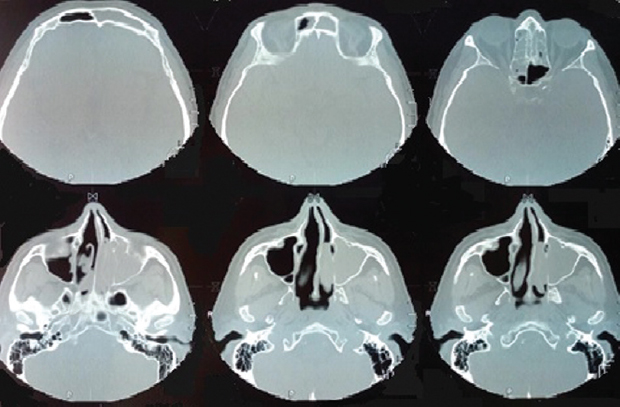

Была проведена терапия преднизолоном в дозе 20 мг/сут, продолжена базисная терапия формотерол + будесонид в дозе 24/800 мкг/сут. Через 3 мес лечения у пациента впервые за много лет восстановилось носовое дыхание и обоняние, удалось снизить дозу и кратность приема бронхолитиков и ингаляционных ГКС, по данным спирометрии ОФВ1 сохранялась на уровне 70 % с положительной реакцией на бронхолитики, улучшилась переносимость физических нагрузок (отсутствуют ангинозные приступы), уменьшились неврологические нарушения. В анализах крови — эозинофилов 1 %, СОЭ — 7 мм/ч. На повторной МСКТ придаточных пазух носа — пристеночное утолщение слизистой оболочки пазух носа и решетчатого лабиринта с обеих сторон. Носовой цикл сохранен. Значительная положительная динамика по сравнению с предыдущим исследованием (рис. 4).

Рис. 4. Мультиспиральная компьютерная томография придаточных пазух носа через 3 мес после лечения. В левой верхнечелюстной пазухе остается кистоподобное образование. Носовой цикл сохранен. Значительная положительная динамика